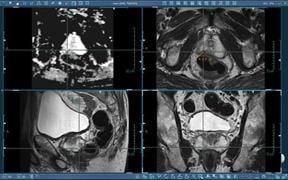

Prostate disease is primarily evaluated by using digital rectal examination (DRE) in combination with other clinical ...

Radiology and Urology team up for successful results. Radiologist John Feller, M.D., medical director of Desert Medical ...